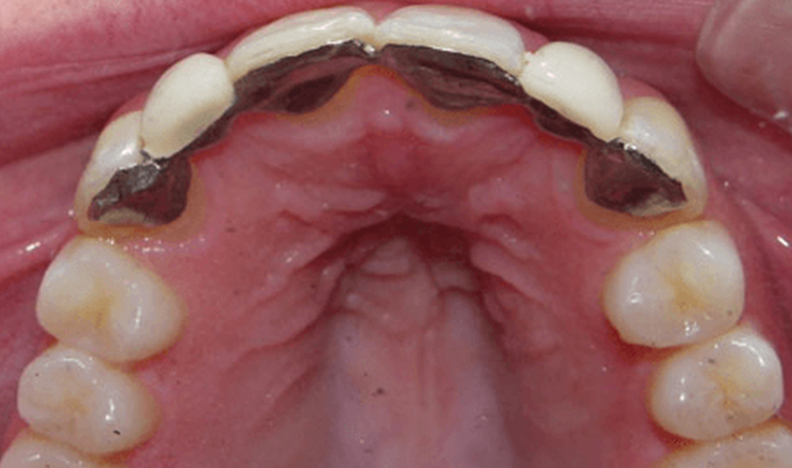

Ultimately, we chose to do two separate bridges out of an all-ceramic material, bonded only to the canines on each side. E.max lithium disilicate bridges from Ivoclar Vivadent 13-X and X-23, cemented by first air abrading the teeth, acid etching with Bisco’s Uni-etch 32% H3PO4 (aq) with BAC, and finally bonding in with Calibra Adhesive Resin cement as per recommended protocol. The results showcase a much more natural smile that’s both brighter and more resilient.